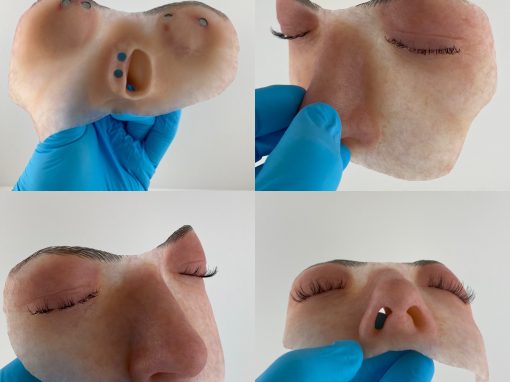

Andrew comes to Hopkins with 10-years of experience in the field of clinical anaplastology, creating custom facial and somatic prosthetics. His services provide treatment options to patients for whom surgical reconstruction alone cannot restore facial features or the appearance of limbs and digits. His custom prosthetic devices allow patients to resume activities of daily living.

Andrew has collaborated with orthopedic and hand surgeons from Duke University and faculty in the School of Dentistry at University of North Carolina at Chapel Hill in challenging reconstructive cases. He creates craniofacial devices including prostheses for large facial defects, custom cranioplasty implants, surgical guides/models, mandible prostheses, and graduated ocular conformers for pediatric patients. Andrew is one of few practitioners worldwide holding certifications in anaplastology as well as mastectomy fitting, pedorthics, orthotic fitting, and ocularistry.

Ear and Eye Prostheses

Patient maxillofacial prosthetics in silicone

Adhesive and Anatomically Retained Prosthetics

Somatic Prosthetics

Osseointegrated Implant-Retained Facial Prosthetics